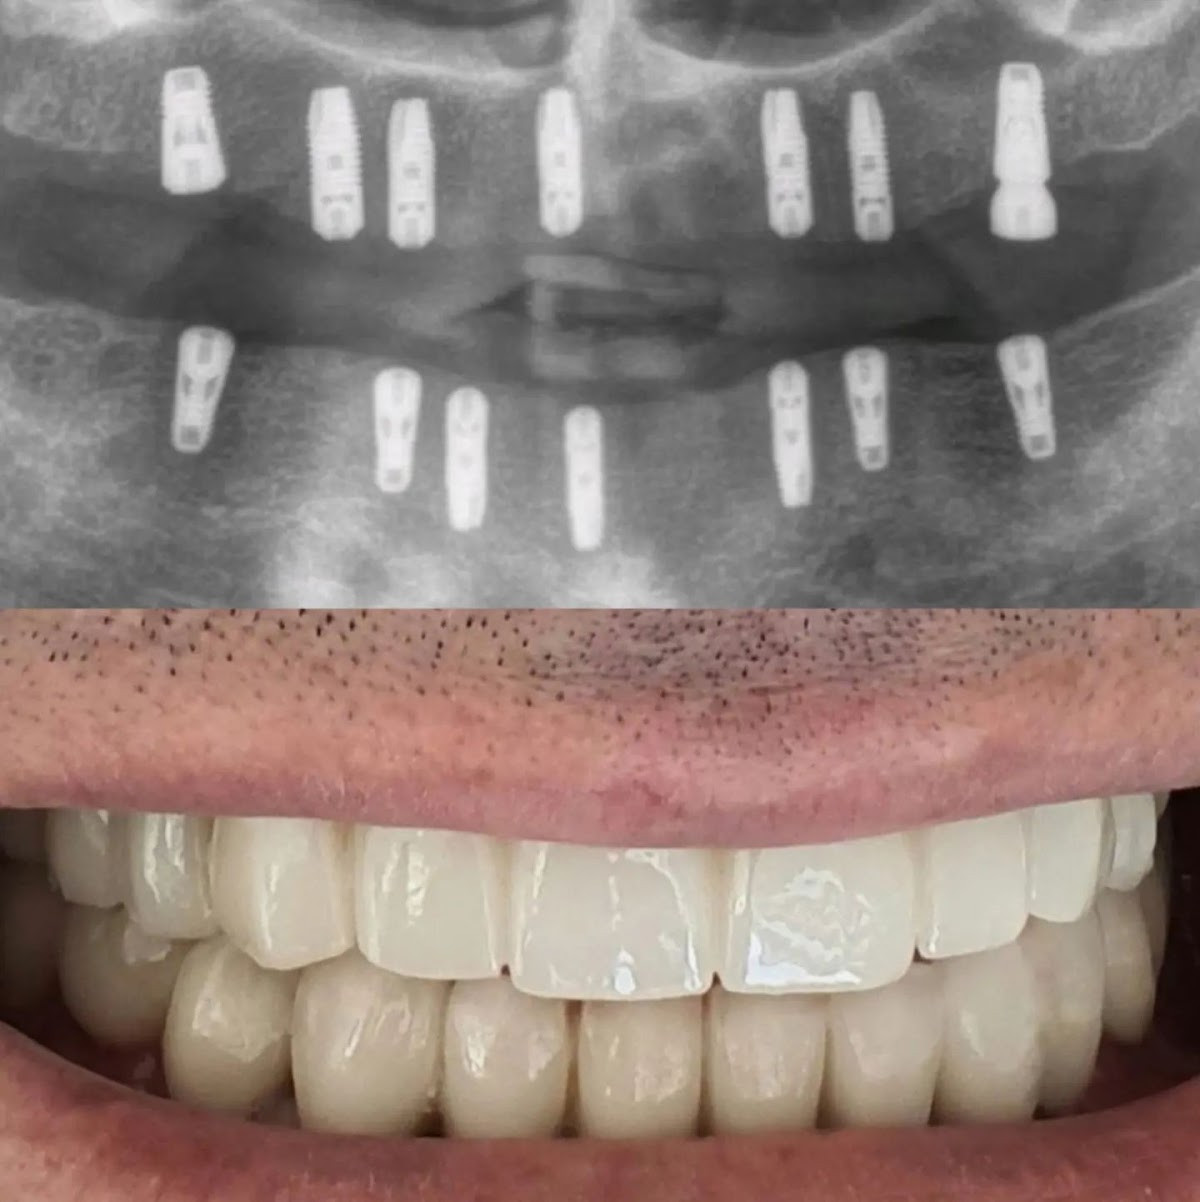

Modern Ağız ve Diş Sağlığı Polikliniği, Manavgat’ın Sorgun Mahallesi’nde konumlanmış, uzman diş hekimleriyle acil ve rutin tedavileri bir arada sunan bir sağlık merkezidir. 2015 yılından beri bölge halkına hizmet veren poliklinik, Manavgat diş hekimi arayışındaki hastalara kapsamlı bir hizmet yelpazesiyle yanıt veriyor. Tam adresimiz Sorgun, 8085. Sokak No:8’dedir ve kolay ulaşım için stratejik bir konuma sahiptir. Aktif olarak çalışan uzman hekim kadrosuyla, çürük tedavilerinden estetik dişçiliğe kadar birçok alanda hastaların sağlığını geri kazandırıyoruz.

Polikliniğimizde Manavgat diş hekimi randevu sistemiyle çalışmanın yanı sıra, Manavgat diş hekimi acil durumlara da anında müdahale ediyoruz. Çocuk diş hekimliği alanında özel eğitim almış hekimlerimiz, minik hastaların korkusuz ve rahat bir şekilde tedavi olmasını sağlıyor. Aynı zamanda diş implantı fiyatları ve diş protezi uygulamalarında da sektördeki en güncel teknolojileri kullanarak, uygun maliyetli ve kalıcı çözümler sunuyoruz. Randevu sistemiyle hastaların bekleme sürelerini minimumda tutarken, diş temizliği ve ağız hijyeni kontrolleri konusunda da düzenli takip imkanı sağlıyoruz. Bölgedeki diğer kliniklerden farklı olarak, 7/24 hizmet sunan Manavgat diş klinikleri arasında yer alıyorsak da, acil durumlar için sabahın erken saatlerinden itibaren randevusuz hastaları kabul ediyoruz.

Uzmanlığımızın temelinde yılların deneyimi yatıyor. Kuruluşundan bu yana yüzlerce hastanın ağız ve diş sağlığını geri kazandırdık ve bu süreçte edindiğimiz tecrübeyle, Manavgat diş hekimi fiyatları konusunda şeffaf ve adil bir politika izliyoruz. Her tedavi öncesi detaylı muayene yaparak, hastaların ihtiyaçlarına özel planlar oluşturuyoruz. Ekibimizdeki diş hekimleri, ulusal ve uluslararası sertifikalarla desteklenen eğitimlere katılmış ve en son teknolojiye sahip cihazlarla donatılmış bir ortamda çalışıyor. Güvenilir diş hekimliği anlayışımız, sadece tedavi değil, aynı zamanda hasta eğitimi ve koruyucu diş hekimliği üzerine de odaklanmamızı sağlıyor.